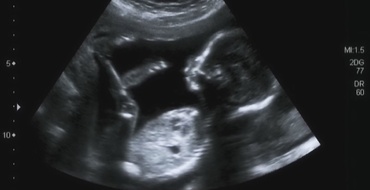

O femeie din Alabama are două utere și poartă câte o sarcină în fiecare dintre ele. Mămica ar trebui să nască la sfârșitul acestui an

Kelsey Hatcher, în vârstă de 32 de ani, din Alabama, are două utere și poartă câte o sarcină în fiecare dintre ele. Femeia ar trebui să devină mamă de fetițe, în preajma Crăciunului....